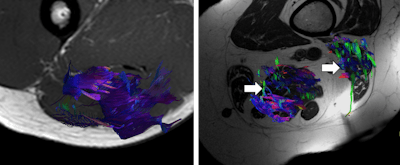

"Skeletal muscle can be evaluated using diffusion-tensor imaging (DTI) techniques," they wrote. "The role of DTI goes beyond the 3D representation of muscles for evaluation of muscular ruptures or for evaluation of inner fibrillar pattern of each muscular group. The data and parameters derived from DTI acquisition may help to determine the degree of muscular involvement by sarcopenia."